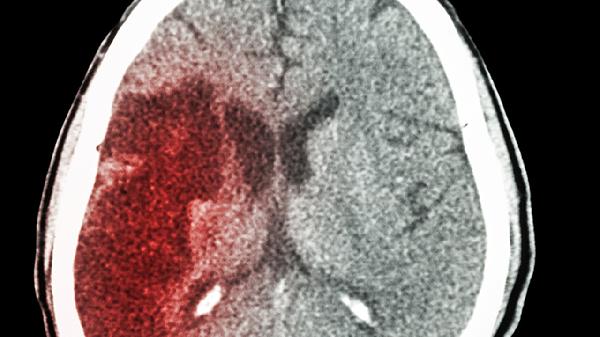

脑溢血就像身体里的定时炸.弹,常常在人们毫无防备时突然引爆。这种急症来势汹汹,留给抢.救的时间窗口往往只有黄金几小时。中老年人作为高发人群,更需要提高警惕。